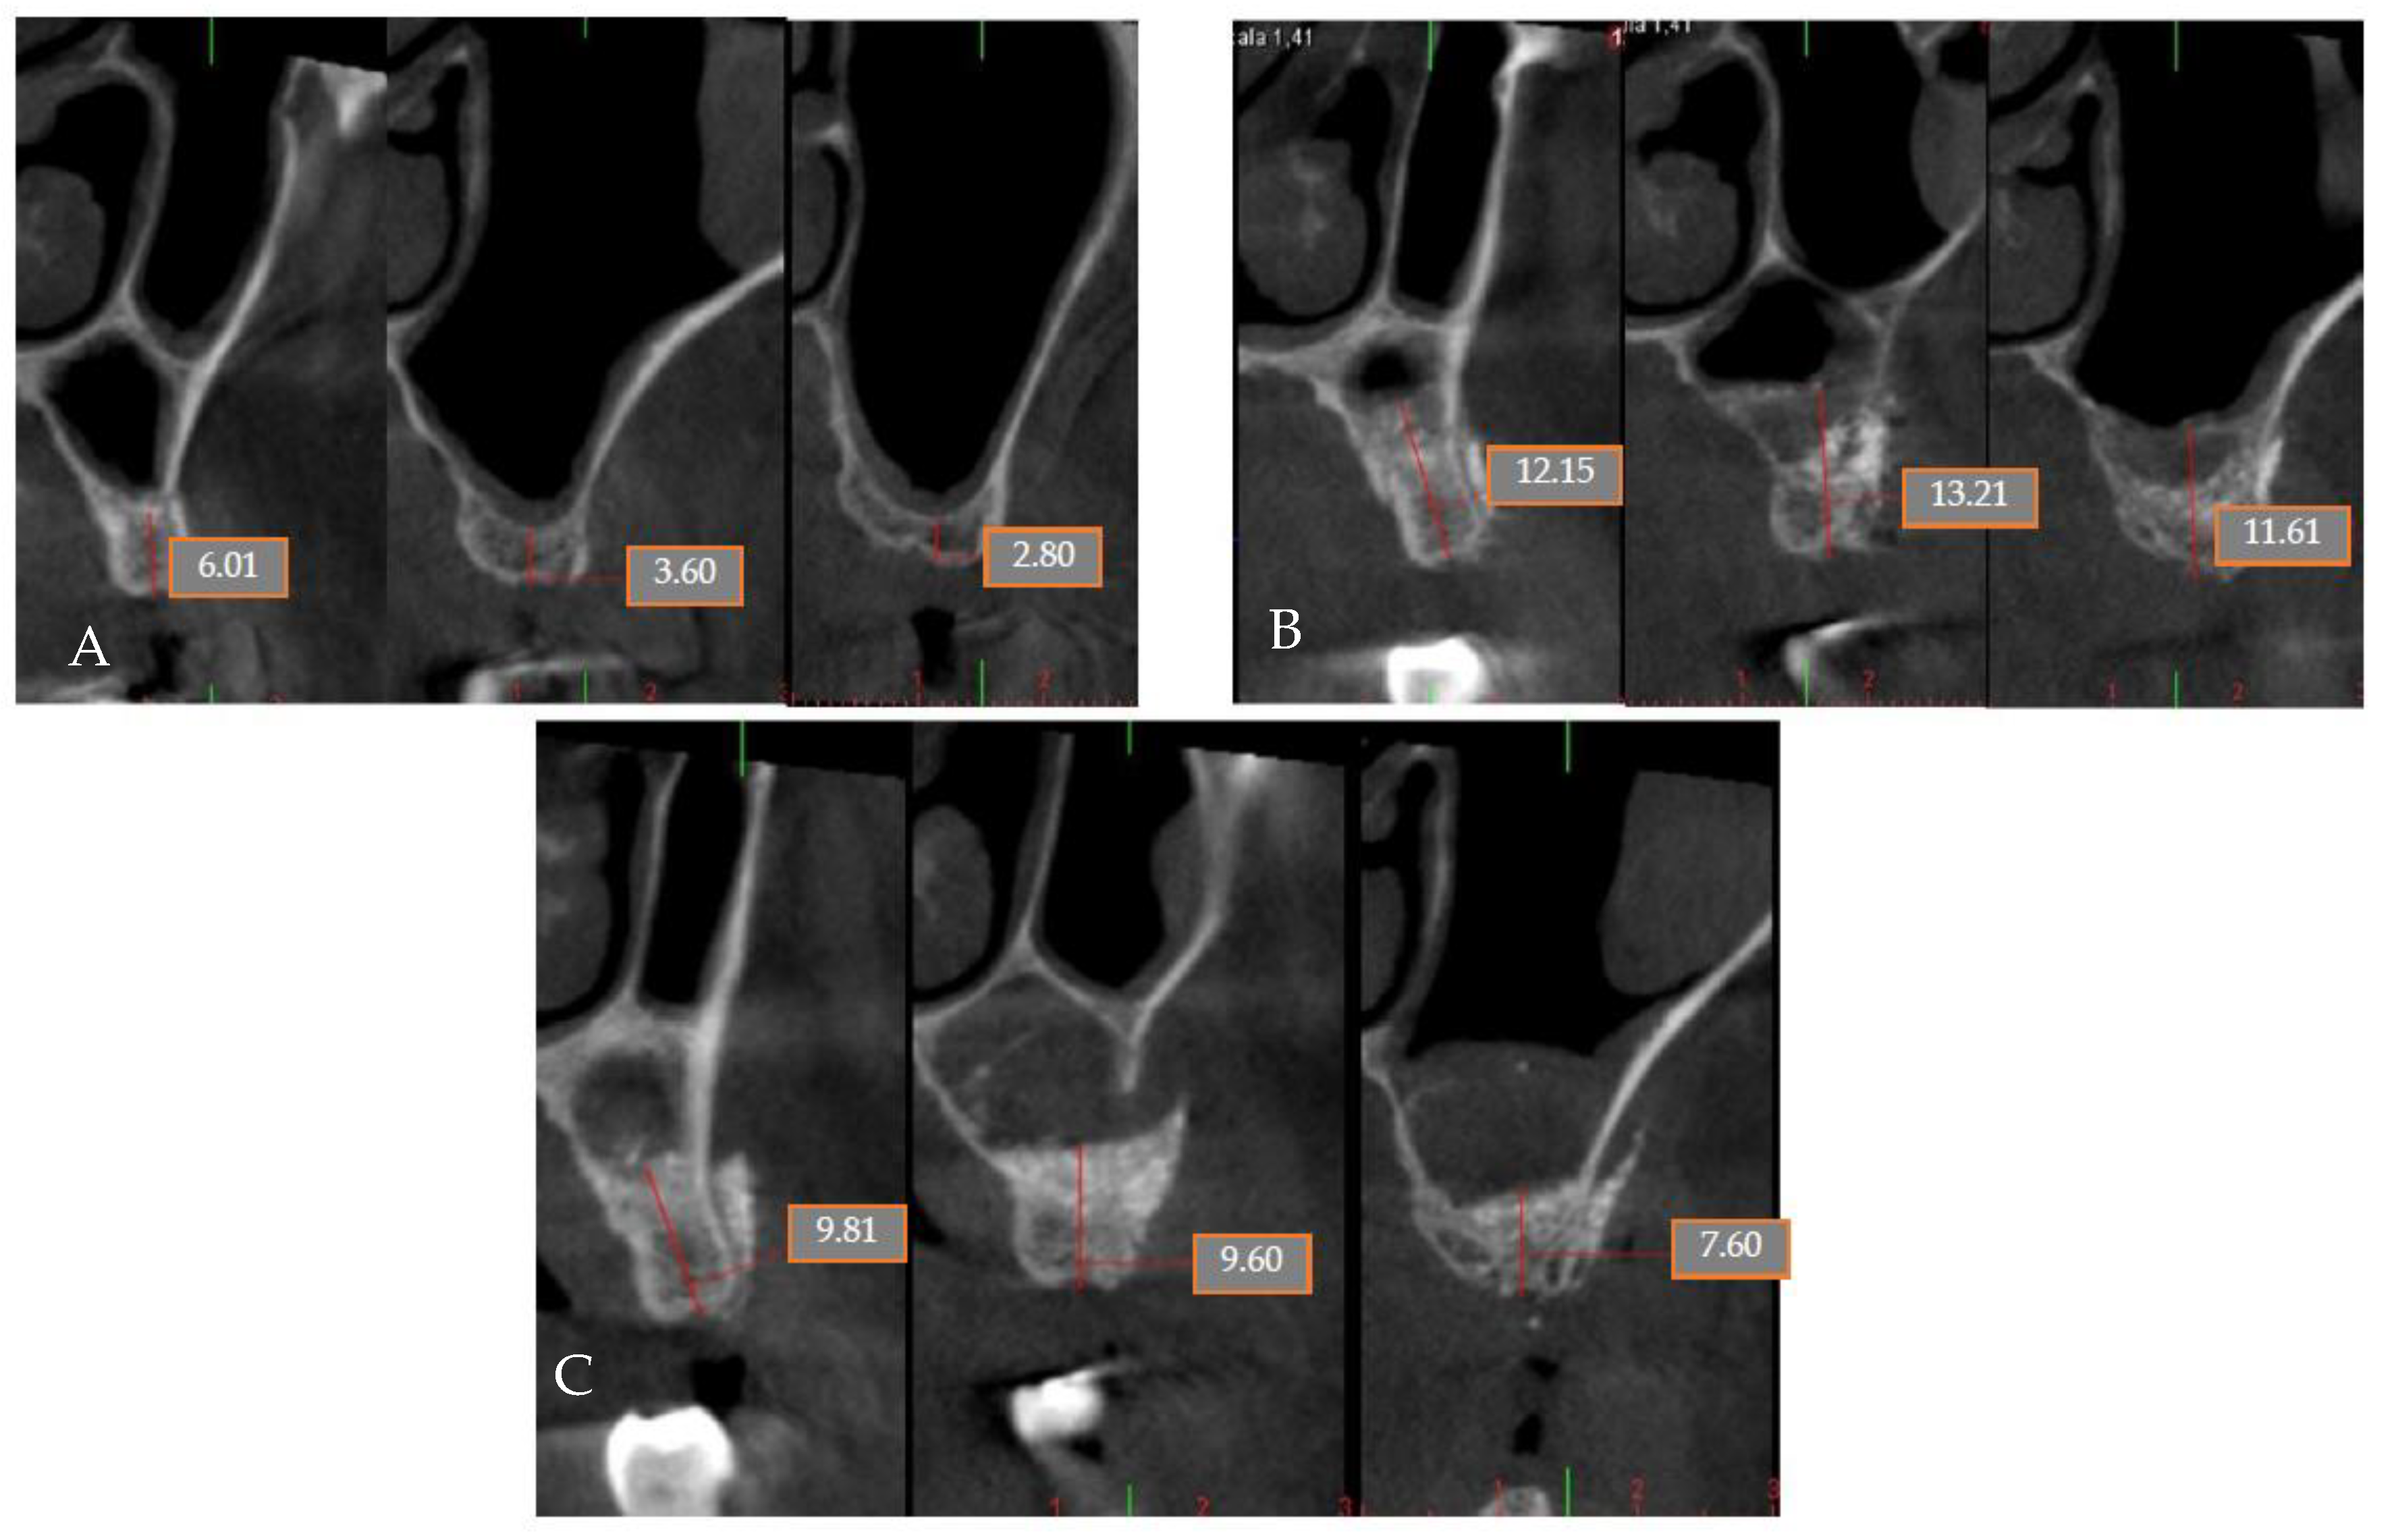

| Laino et al. [34] 2015 CT | n: 27 49–75 = 59 years old | To evaluate the efficacy of calcium sulfate in lateral window sinus lifts. | At 6 months Mean bone height before surgery: 4.04 ± 1.48 Mean bone height in regenerated sites: 12.25 ± 3.20 mm Mean bone height gained: 8.21 ± 1.73 mm | The use of calcium sulfate in lateral window sinus lifts is an effective procedure. | |

| 5 M 64 | NO [-] Sinus lift with lateral window | Yes [No] | G | No | G | No | No |

| 6 M 46 | NO [-] Sinus lift with lateral window | Yes [No] | G | No | G | No | No |